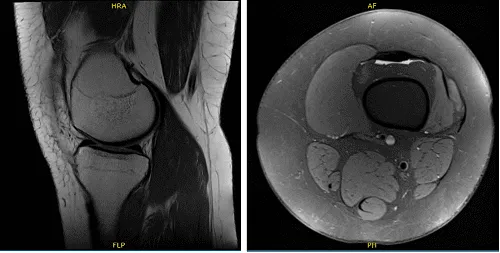

Acordamos realizar una resonancia magnética que mostró que el estado tras la reparación meniscal del desgarro del mango del cubo visto anteriormente con la apariencia es desgarro recurrente y alteración del cuerno anterior asociado al desplazamiento de un colgajo grande y la alteración focal del cuerno posterior hacia la proximidad de la inserción tibial.

Los cambios postquirúrgicos están presentes en la unión meniscocapsular y a través del tejido subcutáneo. También se visualizan portales artroscópicos hacia la grasa infrapatelar. También se observaron una enfermedad degenerativa del compartimento lateral leve y un pequeño derrame articular.

Radiografía de rodilla izquierda